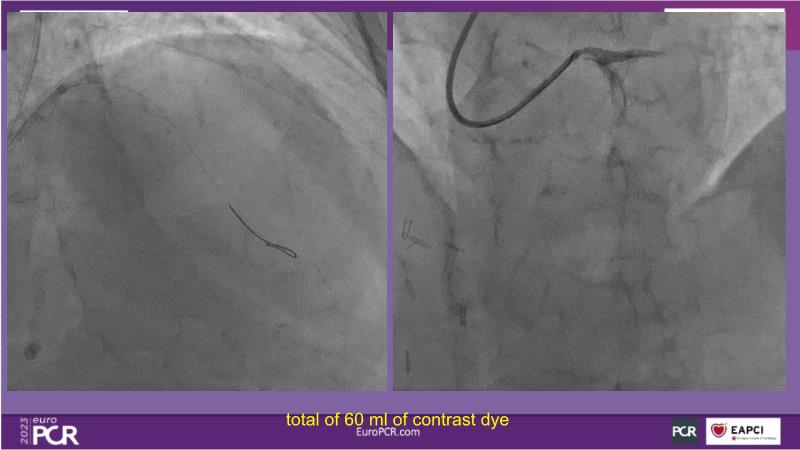

- To receive an in-depth insight into the latest clinical data and experiences on drug-coated balloon usage in in-stent restenosis, de-novo and bifurcation indications